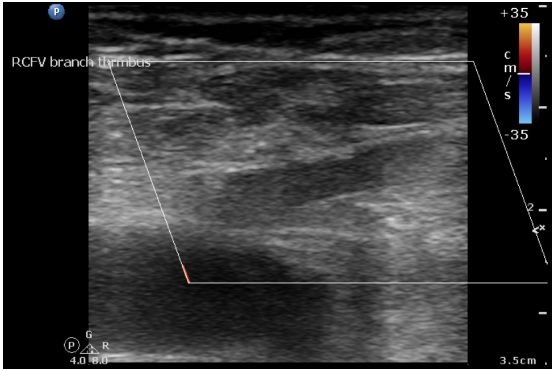

Relevant Catheterization Findings

Carbon dioxide venography revealed patent right popliteal and femoral veins, with total occlusion of the right external and common iliac veins with collateral vein from femoral vein to IVC. The left iliac-femoral stent showed no in-stent restenosis but was positioned from the contralateral wall of the IVC, covering the right iliac vein ostium.